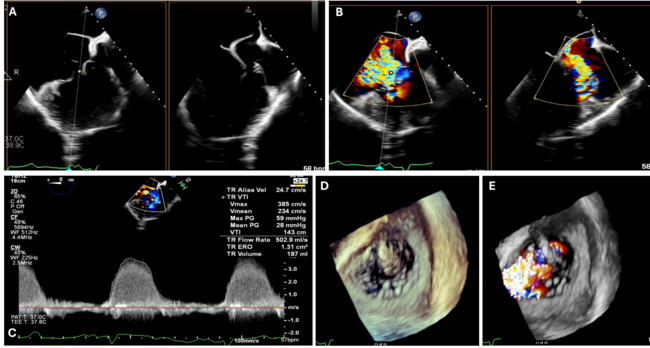

A 36-year-old man with an unrepaired double inlet and double outlet right ventricle, severe pulmonary stenosis, and dextroversion, who was on the heart transplant waiting list, presented with acute heart failure. Echocardiography showed severe right-sided tri-leaflet atrioventricular (tricuspid) valve regurgitation due to a flail anterior leaflet (Figure 1, Video 1). The Heart Team recommended transcatheter edge-to-edge repair as a bridge to a potential future heart transplant.